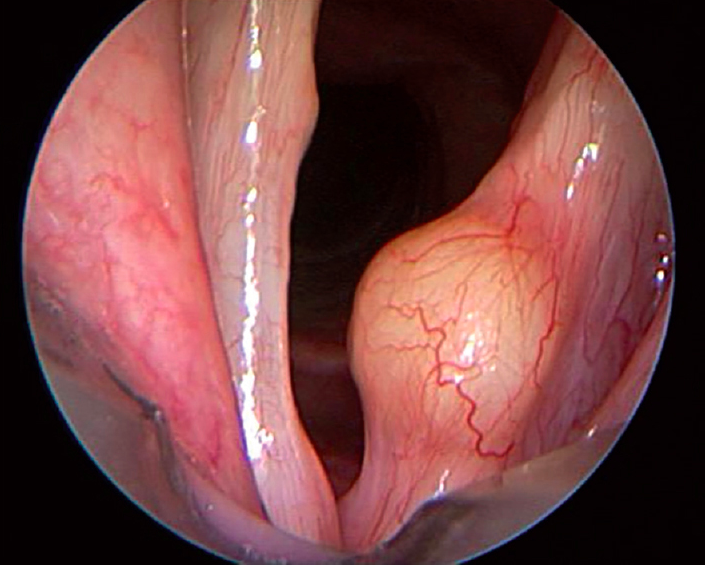

Quiste En Las Cuerdas Vocales, Quiste en las cuerdas vocales, 1.3 MB, 00:57, 20,483, Clinica de la Voz, 2011-02-01T17:40:11.000000Z, 3, QUISTE CUERDA VOCAL - YouTube, www.youtube.com, 1280 x 720, jpeg, WebQuiste de las cuerdas vocales. Un quiste de cuerda vocal es una masa firme de tejido contenida dentro de una membrana (saco). El quiste puede ubicarse cerca de la. WebEn nuestra serie, los quistes de cuerda vocal en los adultos fueron más frecuentes en mujeres (68,3% mujeres versus 31,7% hombres), mientras que en los pacientes. WebEl quiste de cuerda vocal se manifiesta por disfonía permanente. En ocasiones puede ocurrir que algunos tonos de la voz salgan sin problemas pero otras frecuencias de la., 20, quiste-en-las-cuerdas-vocales, Novedades y Muebles WebQuiste de las cuerdas vocales. Un quiste de cuerda vocal es una masa firme de tejido contenida dentro de una membrana (saco). El quiste puede ubicarse cerca de la. WebEn nuestra serie, los quistes de cuerda vocal en los adultos fueron más frecuentes en mujeres (68,3% mujeres versus 31,7% hombres), mientras que en los pacientes. WebEl quiste de cuerda vocal se manifiesta por disfonía permanente. En ocasiones puede ocurrir que algunos tonos de la voz salgan sin problemas pero otras frecuencias de la.

WebLos quistes suelen verse como una masa oval que tiene un contenido transparente o blancoso por dentro de la cuerda vocal). Algunos quistes muy pequeños que se. WebLos quistes de las cuerdas vocales (también conocidos como quistes de las cuerdas vocales) son masas benignas de las cuerdas vocales membranosas . Estos quistes.

WebPuntuación: 4.1/5 ( 32 valoraciones ) ¿Cuáles son algunos de los síntomas o características observables de los nódulos y pólipos de las cuerdas vocales? ronquera. voz. WebLos quistes de las cuerdas vocales son crecimientos que tienen un saco alrededor de un centro semisólido o lleno de líquido. Estos son menos comunes que los. WebQuistes vocal o quistes de las cuerdas vocalesPólipos VocalesNódulos vocalesDisfonía, afonía, voz ronca o ronqueraMicrocirugía laríngea, Cirugía de las cuerdas.

WebUna lesión reactiva de las cuerdas vocales es una masa situada frente a una lesión de las cuerdas vocales, como un quiste o pólipos. Este tipo de lesión se cree que se. WebLas microsinequias son membranas de pequeña superficie (2-4 mm) que unen las cuerdas vocales a nivel de la comisura anterior. La membrana redondea el ángulo. WebOtros nombres: Extirpación de quistes o formaciones cuerdas vocales o epiglotis. Microk¡laringoscópia. Los quistes de cuerdas vocales son casi siempre unilaterales..